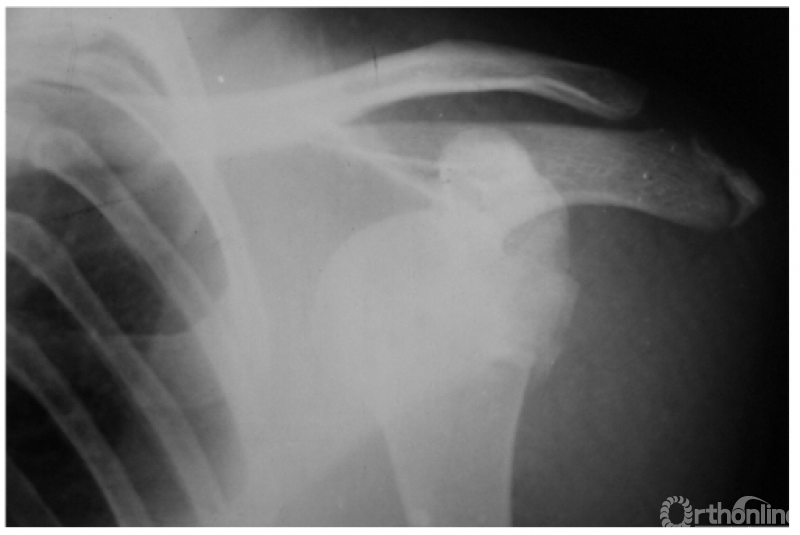

例6:肩关节盂下脱位并外科颈骨折:其肱骨头仍滞留在盂下(如下图)。

例7:肩关节盂下脱位并肱骨干骨折(本病常由于肱骨干骨折的干扰而最易漏诊肩关节的脱位)(如下图)。

二、肩关节外脱位

例1:肩关节外脱位并肱骨外科颈骨折,肱骨头上下倒置,远折端回缩至关节盂处致形成假关节(如下图)。